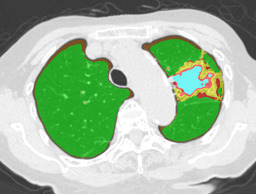

In this paper, we define partial annotation as an annotation format in which only one class is chosen for the annotation and only pixels belonging to the chosen class are annotated per image. For example, in Figure 1(a), although there is ground glass opacity in the image, only consolidation is chosen for annotation and pixels of consolidation are annotated. Partially annotated dataset is less informative for training, however, it is much easier to create compared to fully annotated dataset since annotators only need to focus on one class at a time during the annotation task.

Partially annotated datasets have been utilized previously [8, 9]. In this paper, we propose a new weak supervision technique that fully utilizes partially annotated dataset. Throughout this paper, each DLD pattern is represented or painted in the following colors (CON:cyan, GGO:yellow, HCM:red, EMP:green, NOR:brown.)

Statistics of our dataset are shown in Table 1 and typical images and their annotations for each DLD pattern are shown in Figure 1. In our partially annotated dataset, all the pixels in a slice were manually classified into two classes: dominating DLD pattern and other tissues. In other words, all the pixels in our dataset were assigned one of the labels from either of the two label sets, Lstrong={lCON,lGGO,lHCM,lEMP,lNOR}subscript𝐿𝑠𝑡𝑟𝑜𝑛𝑔subscript𝑙𝐶𝑂𝑁subscript𝑙𝐺𝐺𝑂subscript𝑙𝐻𝐶𝑀subscript𝑙𝐸𝑀𝑃subscript𝑙𝑁𝑂𝑅L_{strong}=\{l_{CON},l_{GGO},l_{HCM},l_{EMP},l_{NOR}\} or Lweak={lCON¯,lGGO¯,lHCM¯,lEMP¯,lNOR¯}subscript𝐿𝑤𝑒𝑎𝑘subscript𝑙¯𝐶𝑂𝑁subscript𝑙¯𝐺𝐺𝑂subscript𝑙¯𝐻𝐶𝑀subscript𝑙¯𝐸𝑀𝑃subscript𝑙¯𝑁𝑂𝑅L_{weak}=\{l_{\overline{CON}},l_{\overline{GGO}},l_{\overline{HCM}},l_{\overline{EMP}},l_{\overline{NOR}}\}. For example, in Figure 1(a), colored pixels were labeled as lCONsubscript𝑙𝐶𝑂𝑁l_{CON} and all the other pixels were labeled as lCON¯subscript𝑙¯𝐶𝑂𝑁l_{\overline{CON}}. In this paper, we call pixels of label lLweak𝑙subscript𝐿𝑤𝑒𝑎𝑘l\in L_{weak} and lLstrong𝑙subscript𝐿𝑠𝑡𝑟𝑜𝑛𝑔l\in L_{strong} as weakly annotated pixels and strongly annotated pixels respectively. Our pixel-wise annotations were created in the following steps. First, up to 3 slices were chosen for the annotation for each HRCT scan and for each slice, one representing DLD pattern was chosen by a radiologist. Second, three radiologists performed pixel-wise binary annotation (e.g. binary annotation between lCONsubscript𝑙𝐶𝑂𝑁l_{CON} or lCON¯subscript𝑙¯𝐶𝑂𝑁l_{\overline{CON}}) for each slice. Finally, the radiologists’ annotations were merged by taking majority classes for each pixel (i.e. pixels labeled as a DLD pattern by more than 2 radiologists became the corresponding DLD pixel). In addition to the DLDs annotation, lung fields were manually segmented under the supervision of radiologists and training and testing were conducted only within the lung fields.

Figure 1: Typical slices for each DLD classes. Slices of HRCT are shown in lung window setting (window-center=-600, window-width=1500) with annotated labels superimposed in transparent colors. Note that even if more than one DLD patterns existed, only one DLD pattern was chosen and annotated for a slice to facilitate the annotation process.